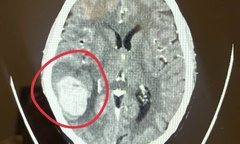

Qua hình ảnh X-quang, bác sĩ ghi nhận tình trạng nhiễm kén sán mật độ dày, kích cỡ tương đương hạt gạo ở các mô mềm vùng đùi và cẳng chân.